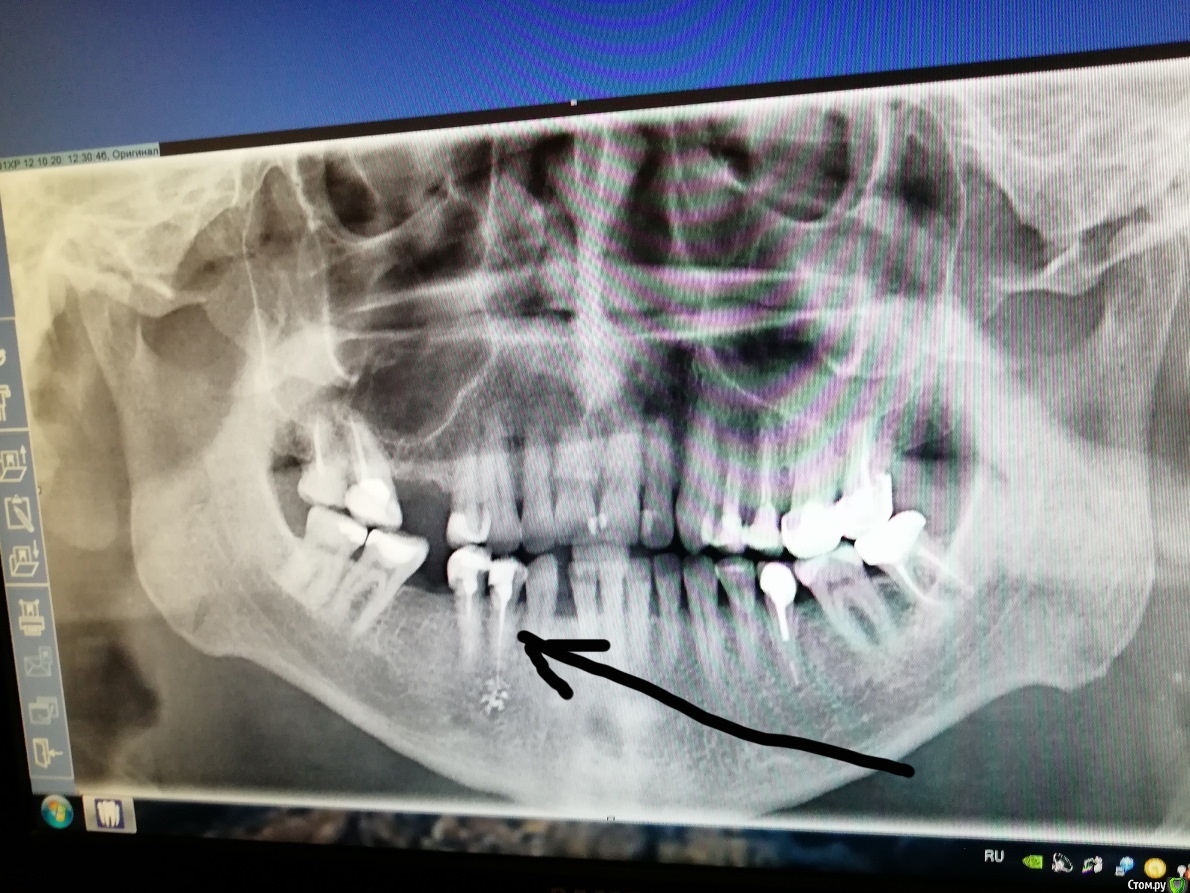

haupman Опубликовано 16 октября, 2020 Поделиться Опубликовано 16 октября, 2020 (изменено) Здравствуйте. 12 или 16 октября поставили временную пломбу и лекарство(пульпит) , на 14 октября назначили лечение. Удалили нерв, запломбировали каналы и зуб. Часов через 6 зуб стал ныть, не острая боль а ныть, как ниткой порой расковырять примерно тоже самое. После лечения сделал сразу снимок, т.к. нужна была консультация по другому зубу и увидел под корнем что лечили зуб- звездочку. Что это? И почему зуб ноет, это так и должно быть(много зубов лечено с удалением нерва но так впервые уже 2 суток) или ошибка врача или что? Спасибо. Изменено 16 октября, 2020 пользователем haupman Ссылка на комментарий

ЛанаМ Опубликовано 17 октября, 2020 Поделиться Опубликовано 17 октября, 2020 Пломбировочный материал вышел за верхушку корня. В течение недели зуб должен адаптироваться. Проконсультируйтесь со своим доктором. 1 Ссылка на комментарий